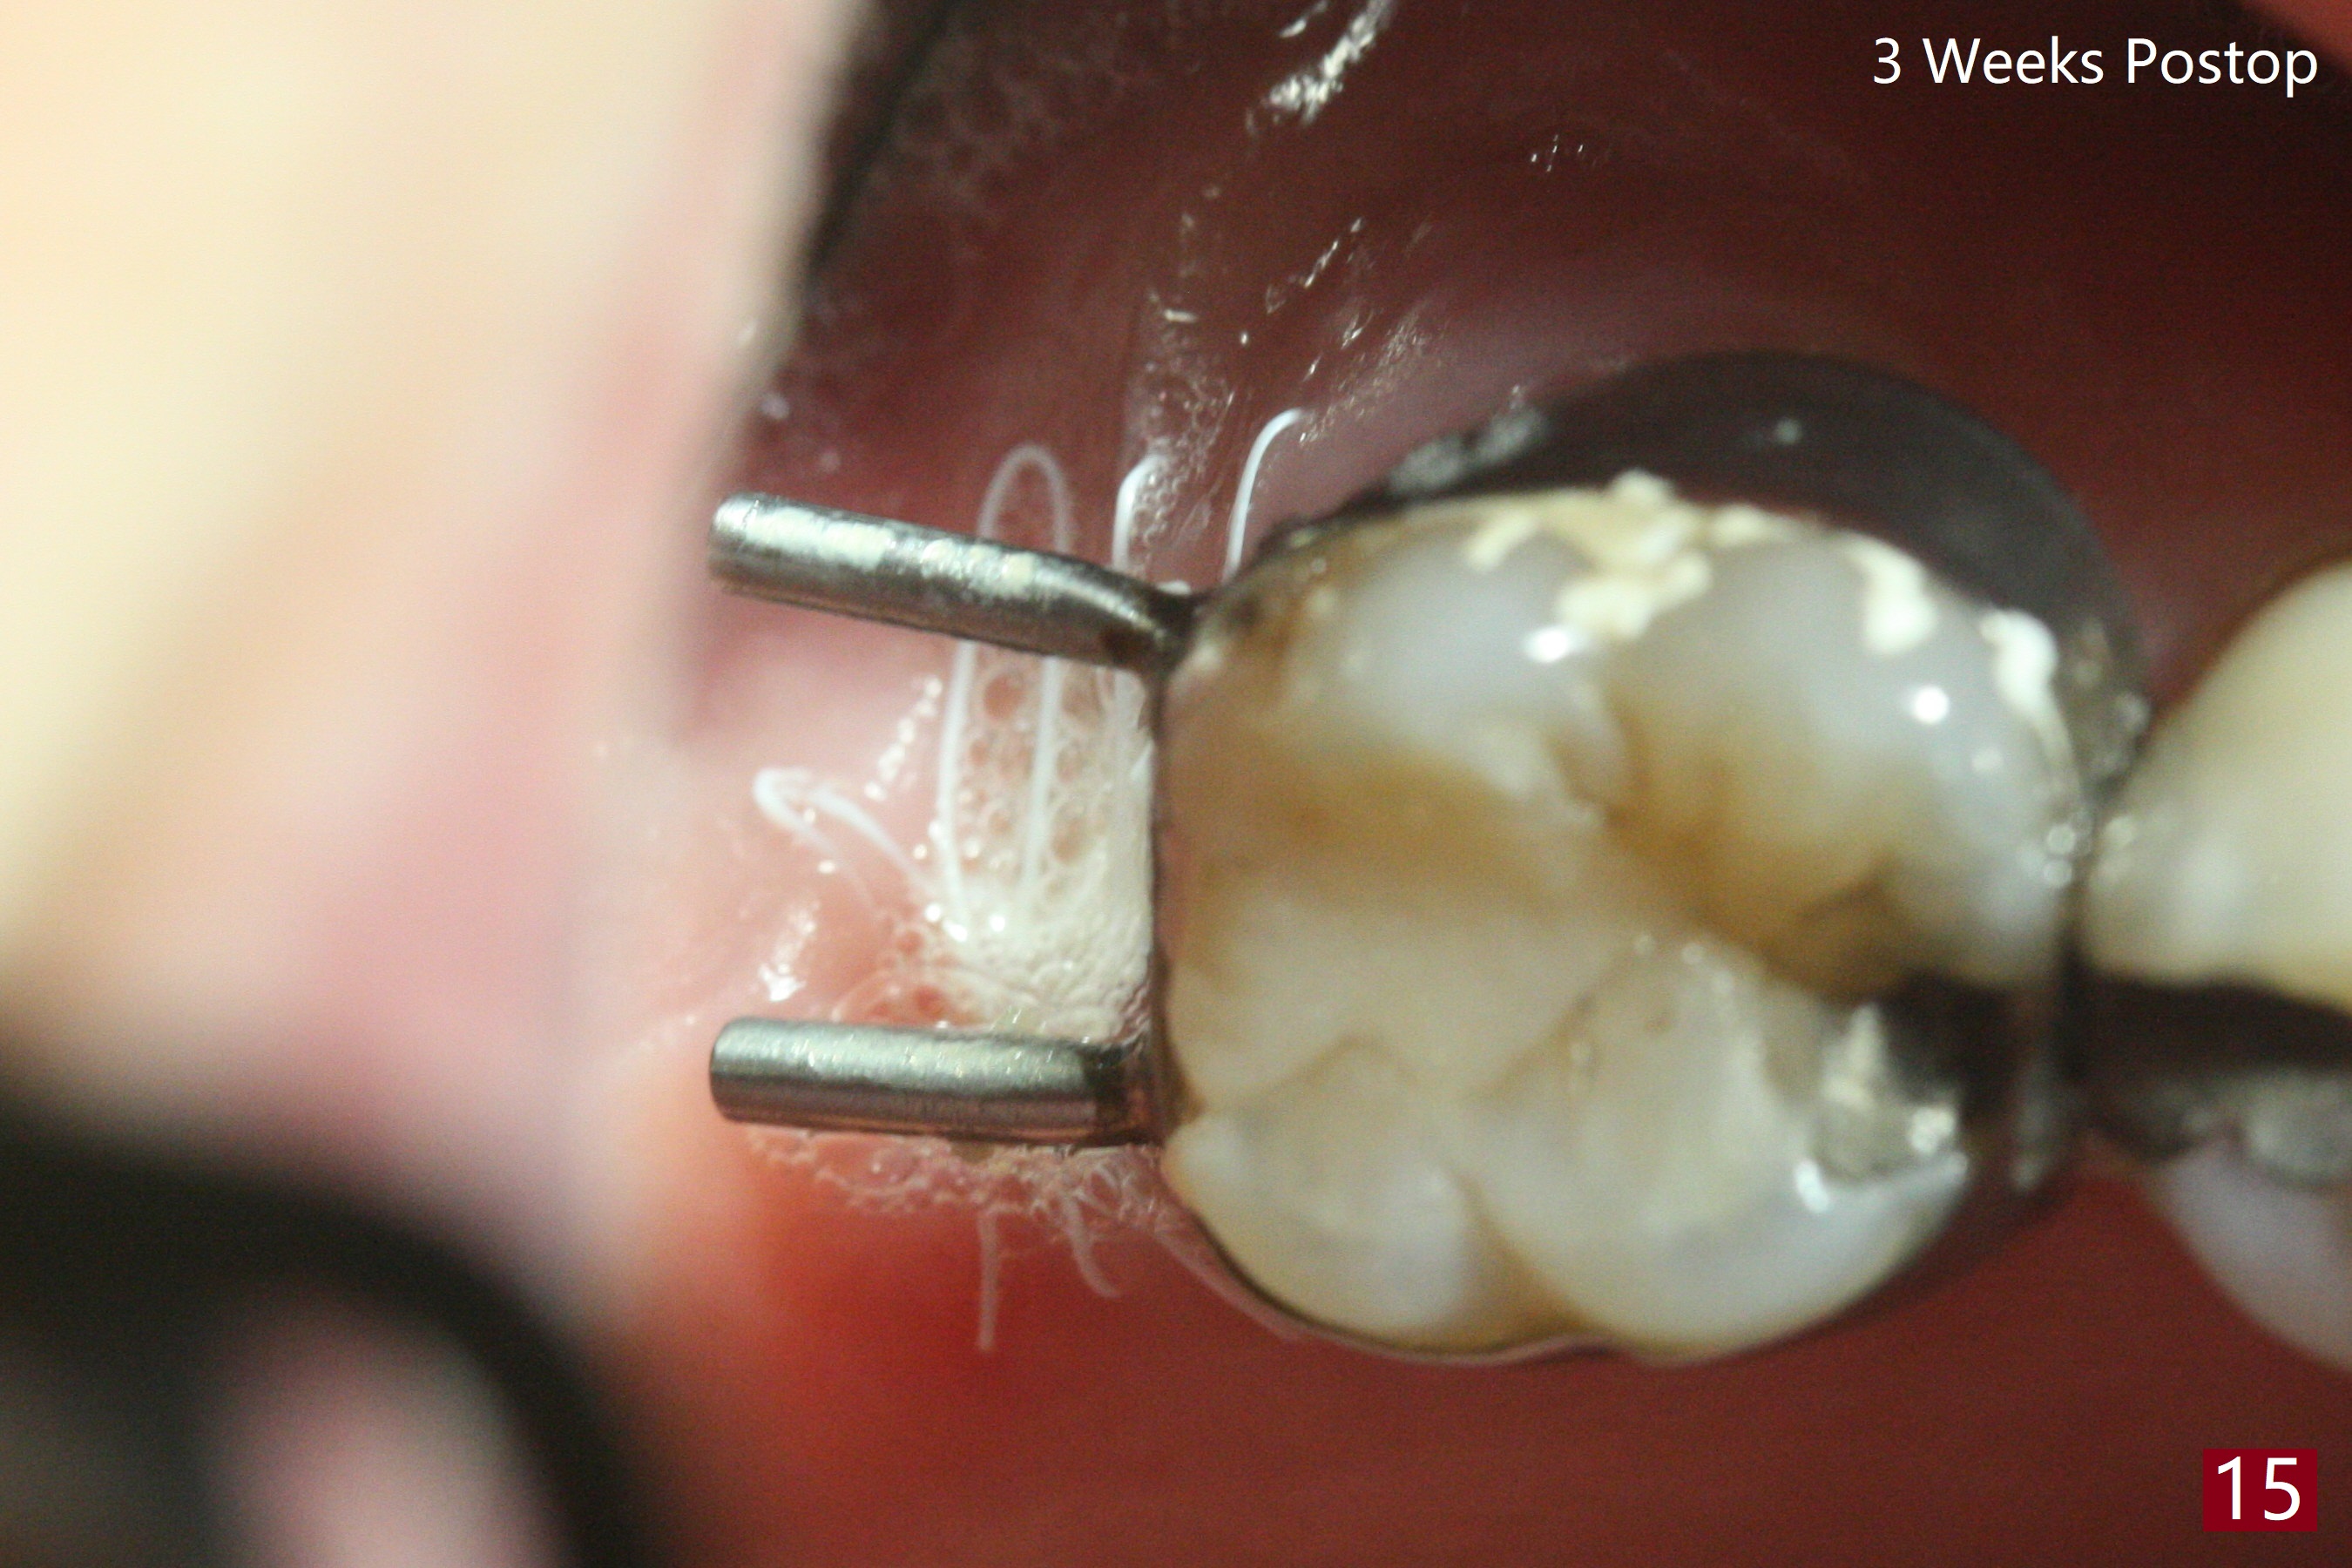

第二磨牙位点保留后,牙周敷料容易脱落,尤其上颌,本文介绍一种方法增加固位。右上七严重牙髓牙周综合征,拔出后使用刮匙除去骨面肉芽组织,颊侧骨板缺失,附着在颊侧粘骨膜上的肉芽组织使用一种叫Stieglitz angled, diamond splinter forceps (德国产,图一,二)撕下来。彻底清除炎性组织必须多次刮治,之间塞入带有灭滴灵(图三:粉剂)和1比50,000肾上腺素局麻药纱布(图四)止血,取出纱布,牙槽窝视野好,继续去除残余的肉芽组织。牙槽窝底部穿孔,用无齿刮匙稍微扩大穿孔后,使用图五下面小的骨粉输送器,将少量骨粉(粘性)送到穿孔处,推入上颌窦(图七:S),之后使用大的骨粉输送器(图五上面),把大量骨粉送到牙槽窝,使用图六上面大的,长的充填器,压实骨粉(图七),骨粉表面放置PRF膜和不可吸收膜(图八),在第一磨牙时安置粘固一个间隙维持器(图九,十),最后铺上牙周敷料(图十一),检查咬合空间,没有干扰。There are sign and symptom of sinusitis 1 week postop; large amount of bone graft retains in the socket by the periodontal dressing and spacer (Fig.12). The sinus membrane (Fig.7 immediate postop) thickens 1 week postop (Fig.13). Augmentin and Medrol Dose Pak are prescribed. 上颌窦炎一周后消失,腭侧牙周敷料丢失,伤口好像正常愈合(图十四)。术后三周牙周敷料由于大量水枪冲洗脱落(图十五)。因为病人需要离城两个月,间隙保持器撤除(图十六),不可吸收膜腭侧稍微外翻 (<),可能有利于术后五周自行脱落。No Deviation SP 下一个病例 位点保留后Xin 导板与张口度 第一磨牙即种 Wei, DDS, PhD, MS 1st edition 09/17/2020, last revision 04/30/2021